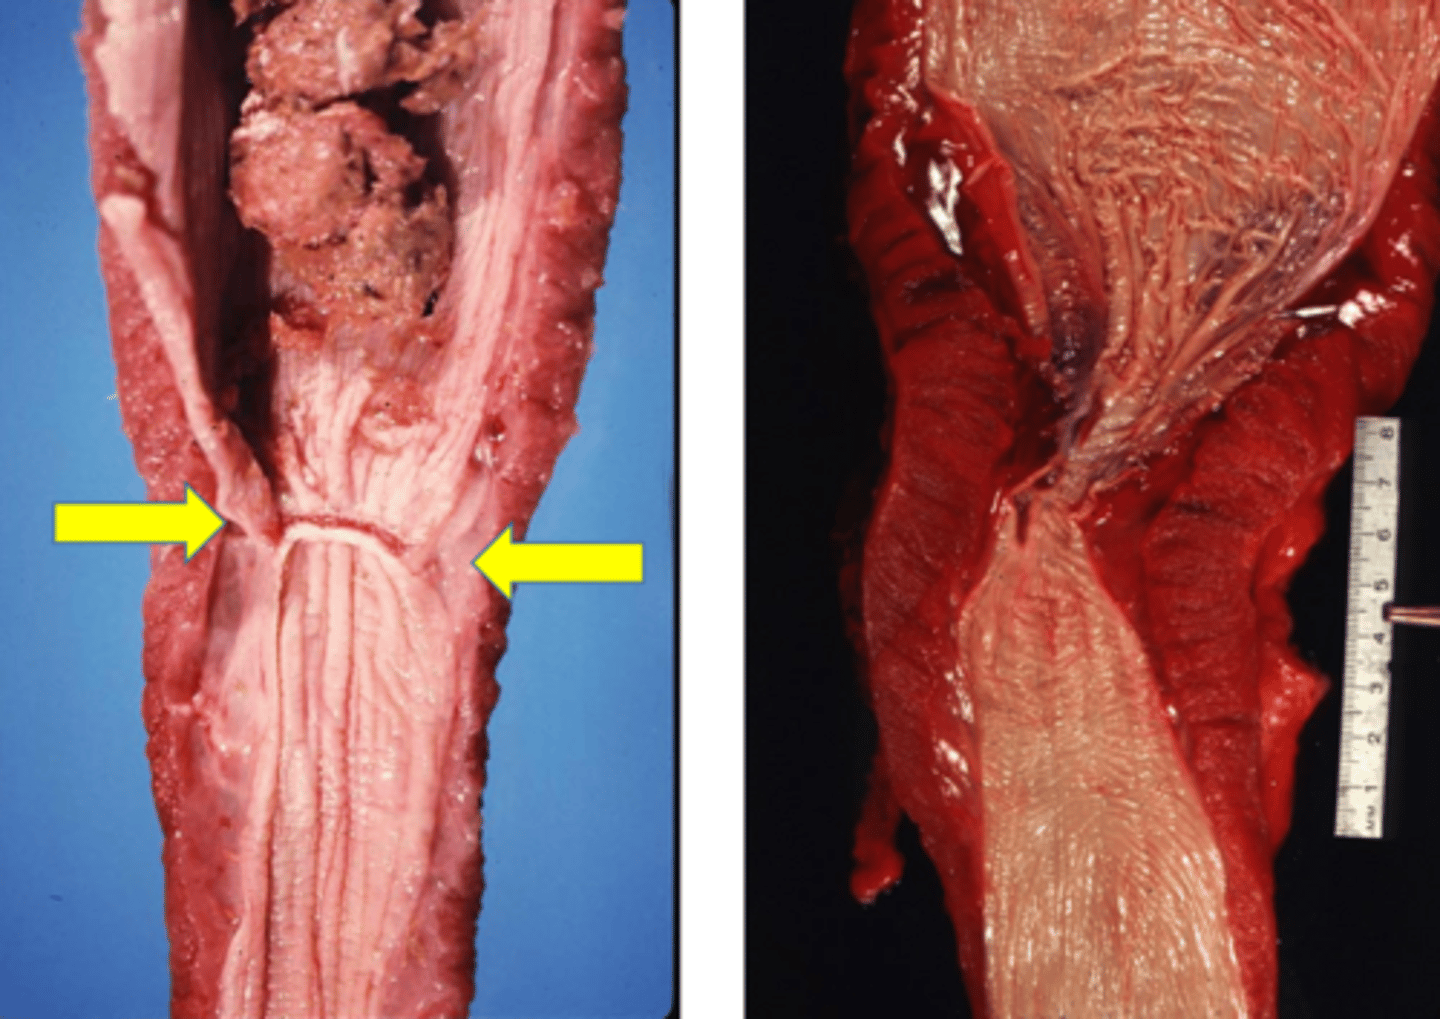

Bloat - (arrow pointing to bloat line where congestion is showing)

Identify the pathology?